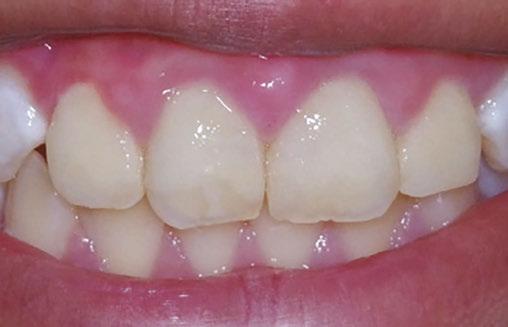

At the postoperative consultation with the mother, we told her the tooth’s complete root formation might prevent its eruption. Orthodontic extrusion of the incisor was ruled out due to his behavior. A conservative approach with observation only was elected as treatment modality. This patient returned for follow-up appointments at ages 10, 11, 12, and 13. During all these visits, the maxillary right permanent central incisor had not erupted. At age 14, due to recurrent dental caries, the patient was taken to the local children’s hospital for dental rehabilitation again. During this second hospitalization, we noticed that the right maxillary central incisor was partially erupted into the oral cavity (Figure 4).

Figure 4: Photograph of area at 14 years old during second rehabilitation under general anesthesia